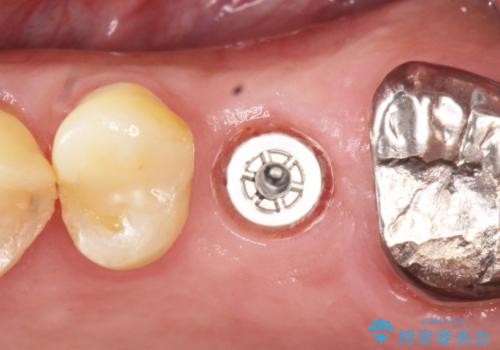

奥歯のインプラント ソケットリフト 60代男性

- 奥歯のインプラントをご希望し、来院された患者様です。

精査したところ上顎骨の厚みが薄かったため、ソケットリフト(上顎洞底挙上術)を併用してインプラント治療を行いました。

インプラントの種類:スプライン ツイスト (保証期間:5年)

クラウンの種類:ベレッツァクラウン (オールセラミック)

固定様式:セメント固定